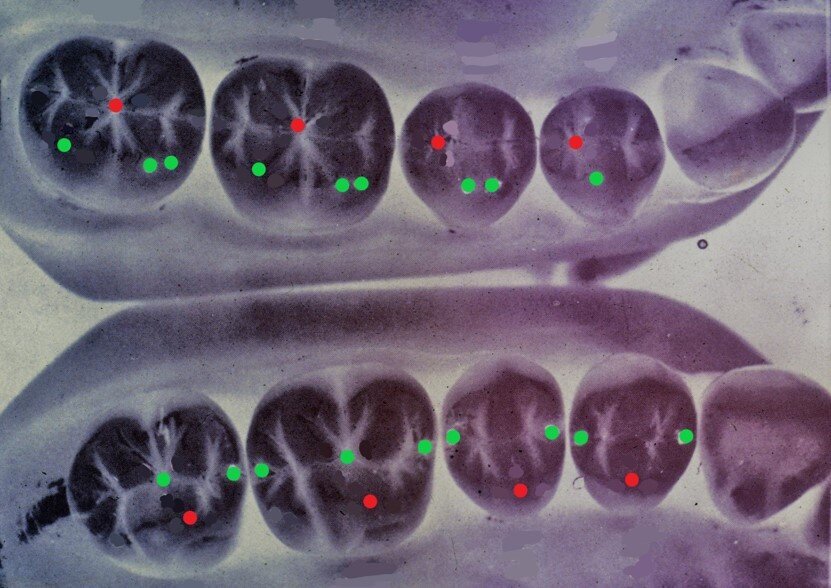

Fig. 2 - I 112 punti di contatto secondo Lundeen: Modellazione di Lundeen di tipo 1=104 punti di contatto; Modellazione di Lundeen di tipo 2=112 punti di contatto.

Fig. 3 - Occlusione semplificata secondo Wiskott: Modellazione di tipo 1= 16 punti di contatto; Modellazione di tipo 2= 36 punti di contatto.